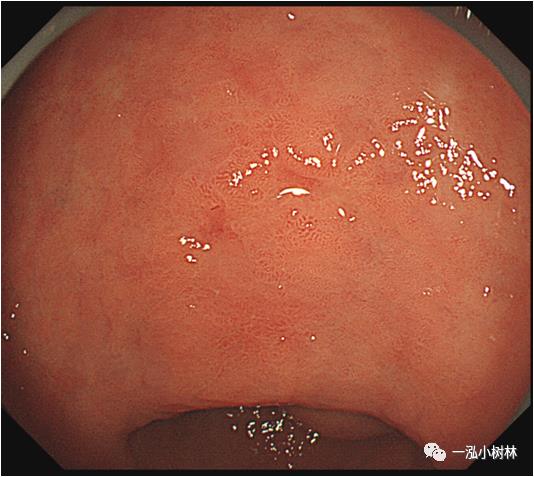

例1 胃窦病变

图1a 白光内镜:胃窦小弯可见IIa+IIc病变,范围2.0cmx1.5cm,微发黄,似胃炎样外观,边界线可疑。